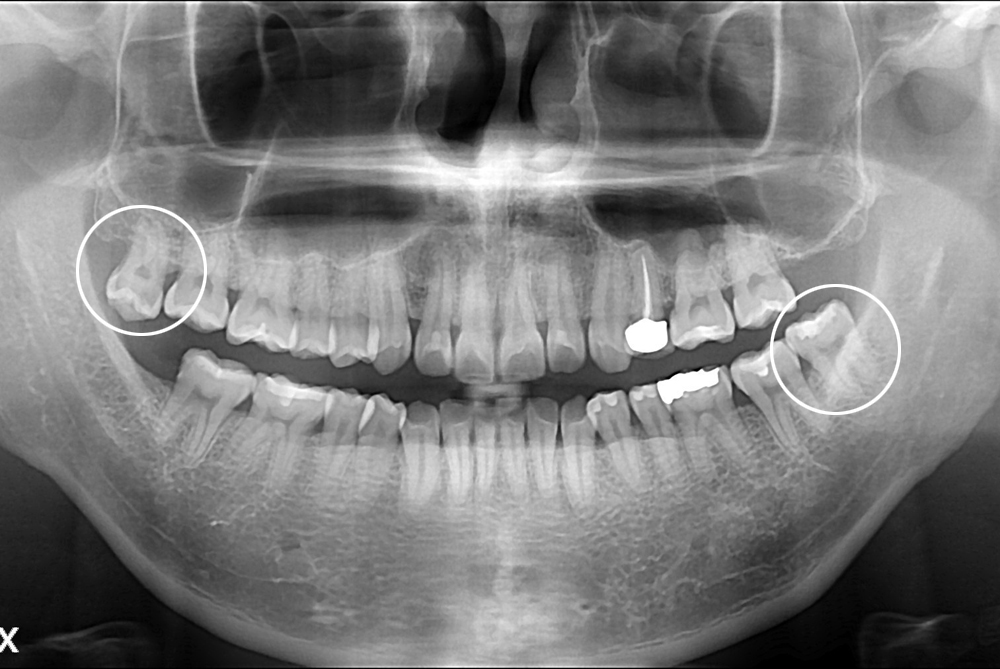

[사랑니] 난발치 사랑니 발치

치료전 : 2017-03-03